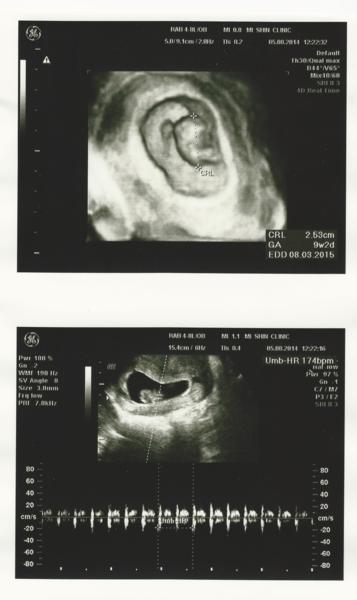

103.08.05

又過了兩個星期

寶寶已經長到2.5公分了

以目前來說進度小小超前

而心跳也增加到174下

(是因為身體小小所以血液回流快嗎?)

這時候的寶寶已經有個雛形了

是可愛的二頭身

頭長出來了

手腳還在發芽

(醫師形容的真妙XD)

而上次產檢的報告也出來了

一切正常

也沒有我原本擔心的地中海型貧血

可喜可賀

下次檢查是8/27

自費檢查唐式症跟SMA

而例行產檢則是排在9/6

聽說這時候就可以看出是男是女

還有手指頭的發育

真令人期待~